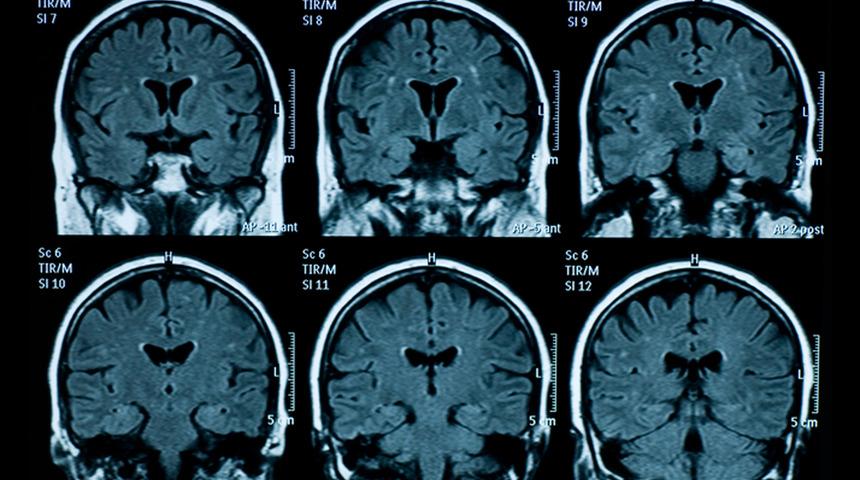

Estonya'nın Tartu kentindeki Raul Vicente Üniversitesi'nden nörobilimciler, araştırma sırasında esasında 87 yaşındaki bir epilepsi hastasının beyin dalgalarını ölçüyordu. Ancak hasta, bir elektroansefalografi (EEG- beyin akım yazımı) cihazına bağlı olduğu sırada kalp krizi geçirerek öldü.

Hastanın öldüğü sırada beyninde yaşanan aktiviteler ise 900 saniye boyunca EEG tarafından kaydedildi. Kalbin durmasından önceki ve sonraki 30'ar saniyeyi inceleyen araştırmacılar, genellikle rüya görürken ve hafızayla bağlantılı aktivitelerde artan gama dalgalarında bir yükselme tespit etti. Bu süreçte aynı zamanda, delta, theta, alfa ve beta dalgalarında da artış görüldü. Araştırmacılar, gama dalgalarının konsantre olmak, rüya görmek, meditasyon, hafıza yenileme ve bilinç algısı gibi yüksek bilişsel fonksiyonlarla bağlantılı olduğunu vurguladı.